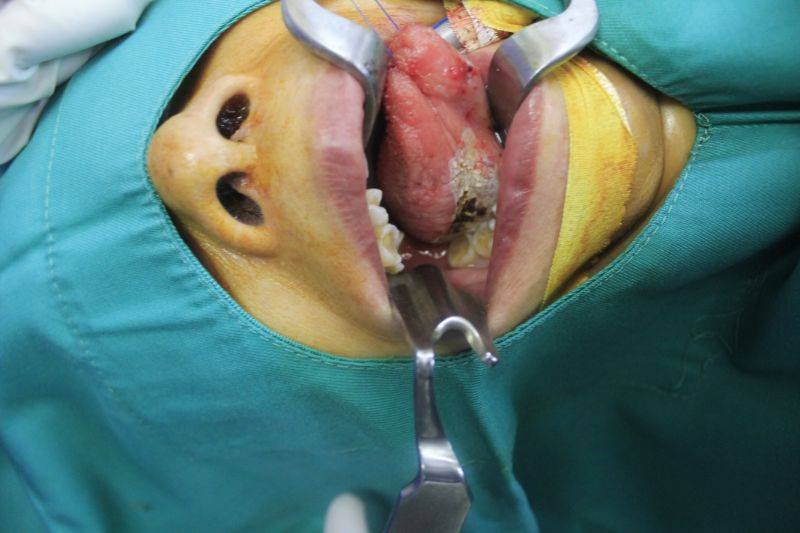

Bệnh nhân N.(60 tuổi, ở Đông Sơn, Thanh Hóa) nhập viện trong tình trạng nuốt vướng, kèm rát vùng dưới lưỡi. Bệnh nhân đã điều trị nội khoa nhưng không đỡ. Các bác sĩ khoa Tai mũi họng đã khám và phát hiện có mảng bạch sản dưới lưỡi bên phải, kích thước tương đối lớn 2x3cm. Các bác sĩ chỉ định phẫu thuật cắt tổ chức bạch sản lưỡi cho bệnh nhân.

PGS.TS Lê Minh Kỳ - Khoa Y dược, ĐHQG Hà Nội – chuyên gia cao cấp của Khoa Khám bệnh theo yêu cầu và quốc tế - Bệnh viện E, là người trực tiếp tiến hành ca phẫu thuật này cho biết: Kỹ thuật thực hiện ca bệnh rất đơn giản. Các bác sĩ đã thực hiện phẫu thuật cắt hớt niêm mạc lưỡi do bạch sản bằng laser cho bệnh nhân.